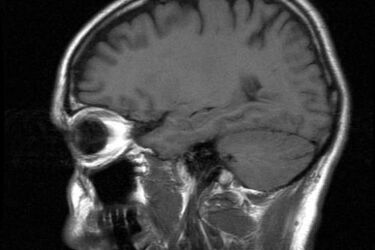

Fot: sxc.hu

Trwa II Tydzień Profilaktyki Nowotworów Głowy i Szyi. W związku z tym, przez dwa dni w białostockich szpitalach będzie można wykonać specjalistyczne badania bez skierowania.